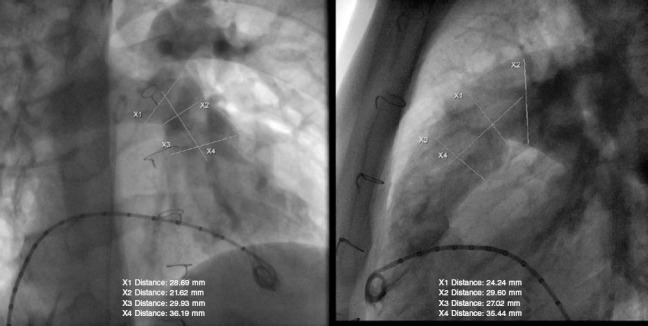

前言和目的:先天性心脏缺陷合并右心室流出道狭窄的手术常导致明显的肺返流,长期需要肺动脉瓣置换术。尽管发展了球囊式可膨胀假体,但原生RVOT经常扩张超过这些瓣膜允许的最大直径。为了允许经皮肺动脉瓣植入术(PPVI)在这些患者中,临床试验已经开始使用自膨胀假体,包括PULSTA瓣膜。本研究的目的是报告在三家西班牙医院使用该瓣膜的初步经验。方法:描述性研究采用PPVI配合PULSTA假体治疗先天性RVOT合并肺返流患者的效果。结果:纳入10例患者,平均年龄15±2.8岁。所有患者的植入都很成功,在手术过程中没有发生重大并发症。平均随访时间18个月[范围,2-35个月]。8例患者在6个月时进行心脏磁共振检查,发现舒张末期平均容积(131.7±31.7 mL/m2 vs 100.3±28.9 mL/m2)和收缩末期平均容积(68±20.8 mL/m2 vs 57±18.5 mL/m2)减少。结论:PULSTA假体是一种安全、可行、有效的替代方案,可用于原发性扩张性RVOT患者的PPVI。由于可用的随访数据有限,需要进一步的研究来评估其长期安全性和耐久性。

Introduction and objectives: Surgery for congenital heart defects with right ventricular outflow tract (RVOT) stenosis often results in significant pulmonary regurgitation, requiring pulmonary valve replacement in the long term. Despite the development of balloon-expandable prostheses, the native RVOT frequently dilates beyond the maximum diameters allowed for these valves. To allow percutaneous pulmonary valve implantation (PPVI) in these patients, clinical trials have been initiated with self-expanding prostheses, including the PULSTA valve. The aim of this study was to report the initial experience with this valve at three Spanish hospitals.

Methods: Descriptive study presenting the results of PPVI with the PULSTA prosthesis in patients with native RVOT and pulmonary regurgitation.

Results: We included 10 patients with a mean age of 15 ± 2.8 years. The implantation was successful in all patients, with no major complications occurring during the procedure. The mean length of follow-up was 18 [range, 2-35] months. In 8 patients, cardiac magnetic resonance was performed at 6 months, revealing a reduction in mean end-diastolic volume (131.7 ± 31.7 mL/m2 vs 100.3 ± 28.9 mL/m2) and end-systolic volume (68 ± 20.8 mL/m2 vs 57 ± 18.5 mL/m2).

Conclusions: The PULSTA prosthesis offers a safe, feasible, and effective alternative for PPVI in patients with native dilated RVOT. Due to the limited available follow-up data, further studies are needed to assess its long-term safety and durability.